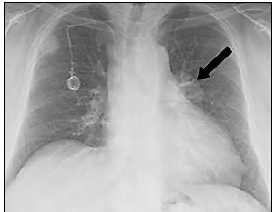

Observe a radiografia torácica, com um achado ressaltado pela seta:

Sobre a imagem anterior, é correto afirmar que observa-se